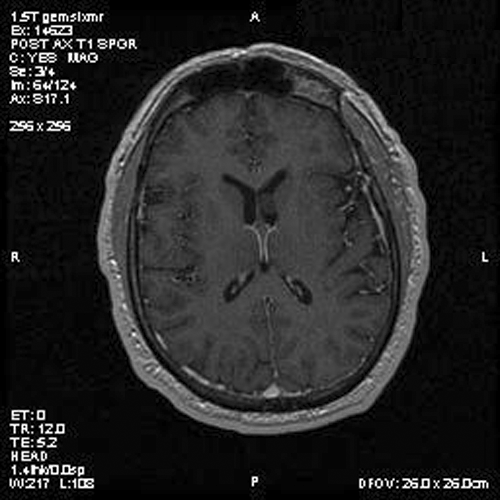

Panel A is T1-weighted post contrast MR image, Panel B is a SPGR T1-weighted post contrast MR image and Panel C is FSE T2-weighted image. Panel D and E are taken from cytologic preparation from intraoperative consultation. Panel F to H are taken from frozen sections. Panel I to L are taken from paraffin section.

Image of the case: In the left frontal horn there is a well demarcated, subependymal mass measuring approximately 1.1 x 0.5 cm which is relatively hyperintense to white matter on T1-weighted image (Panel A and B) as well as T2-weighted image (Panel C) sequences. It does not enhance on the post contrast images. There is no obstruction of the foramen of Monro.

Typically, subependymoma occur as a fungating mass that protrudes into the ventricle. A mild to sometime significant hydrocephalus can be caused by these tumors. On T1-weighted images, they have intensity similar to that of the surrounding white matter. T2-weighted images usually do not demonstrate significant edema around these tumors. Some of its properties also varies according to the locations. In tumors arising in the fourth ventricle, calcification and heterogeneous contrast enhancement are common; whereas these findings are rare in subependymomas arising in the lateral ventricles 6.